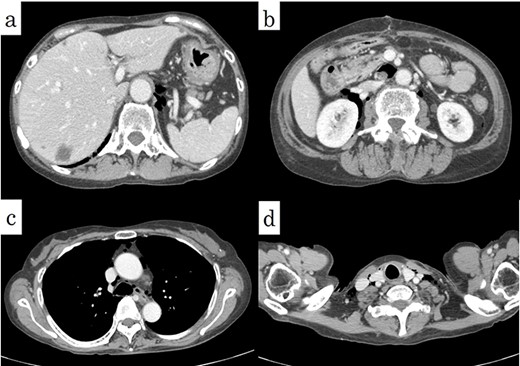

On chest and abdominal CT, free gas was observed in the entire abdominal cavity (Fig. 1a), and extensive emphysema was also observed in the retroperitoneum (Fig. 1b). In addition, it was observed from the mediastinum to both sides of the necks (Fig. 2).

Postoperatively, the patient was withdrawn from the ventilator on hospital Day 1. Chest and abdominal CT performed on hospital Day 8 confirmed a marked reduction in emphysema from the retroperitoneum to the mediastinum and neck (Fig. 5). The patient’s postoperative course was good, and she was discharged on hospital Day 21.

Postoperative CT showed a decrease of the pneumoretroperitoneum and pneumomediastinum (arrows).